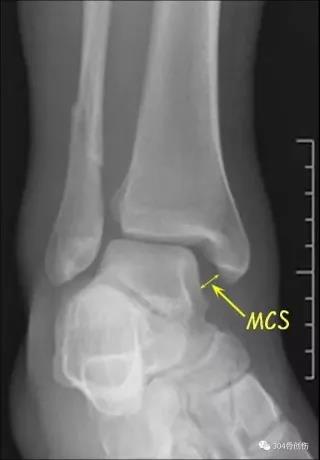

下胫腓联合损伤诊断

术中判断外旋应力试验::内侧间隙增大超过2毫米提示损伤Hook test:在内外踝骨折固定后,用尖钩向外拉腓骨,如腓骨向外移动大于4mm,则表明下胫腓联合韧带完全撕裂

三角韧带断裂判断

三角韧带修复专家共识1.做不做?具有以下情况建议做:年轻活动量大,尤其精英运动员;踝关节内侧间隙大于5mm以上;踝关节内侧肿胀和淤血很严重;CT见踝关节内侧间隙有小骨块;MRI示三角韧带深浅层完全断裂;踝骨折固定后内侧间隙过大或不稳。